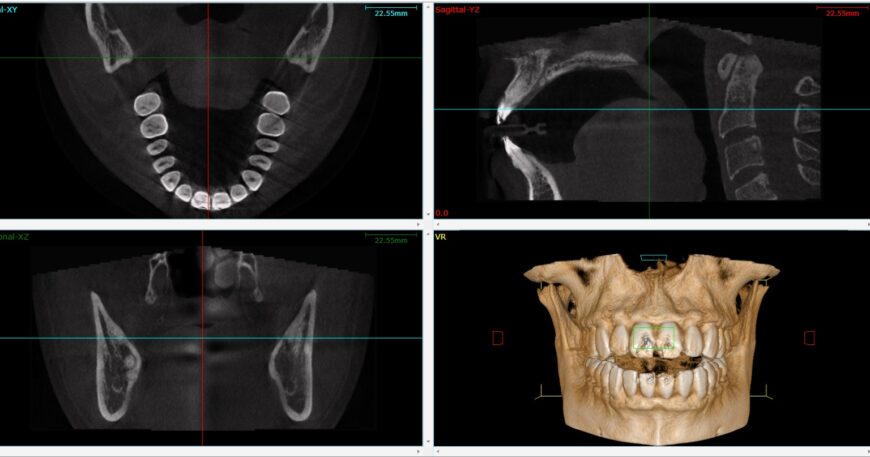

يعد فحص اشعة CBCT للاسنان، أو التصوير المقطعي المحوسب بالحزمة المخروطية، أحد أحدث تقنيات التصوير ثلاثي الأبعاد للأسنان والفك، فيعتمد هذا الفحص على التقاط 150 إلى 200 صورة دقيقة لرأس المريض في أقل من دقيقة واحدة باستخدام شعاع أشعة سينية مخروطي الشكل، ثم تدمج هذه الصور لإنشاء نموذج ثلاثي الأبعاد مفصل، فيمكن من خلال هذا النموذج الاطلاع بدقة على الأسنان، وعظم الفك، والجيوب الأنفية، بالإضافة إلى الأعصاب والأنسجة الرخوة، كما يشمل هياكل الأذن والأنف والحنجرة،

يعتمد هذا الفحص على التصوير المقطعي المحوسب بالأشعة السينية باستخدام حزمة مخروطية الشكل، وهو ما يعرف باسم اشعة CBCT للاسنان (Cone Beam Computed Tomography)، وتعد هذه التقنية أحدث تطور في تصوير الأسنان مقارنة بالأشعة التقليدية ثنائية الأبعاد، سواء داخل الفم أو الأشعة البانورامية، فتوفر CBCT رؤية دقيقة ثلاثية الأبعاد للأسنان والفك والأنسجة المحيطة، مما يمكن الدكتور أحمد ذكري، أفضل دكتور حشو أسنان، من تشخيص الحالات بدقة فائقة ووضع خطة علاجية متكاملة وفعالة.

- التصوير المجسم ثلاثي الأبعاد: يتيح رؤية الأنسجة بشكل ثلاثي الأبعاد وبدقة أكبر مقارنة بالطرق التقليدية، مما يحسن من دقة التشخيص.

- جودة صور عالية: يوفر CBCT صورا ثلاثية الأبعاد للأسنان، الوجه والفكين بجودة ممتازة، تساعد على تقييم شامل للحالة.

- صور تشخيصية واضحة: النظام ينتج صورا دقيقة تتيح للطبيب اتخاذ قرارات علاجية محسوبة بدقة عالية، مع إمكانية التحكم الكامل في التقاط الصورة التشريحية.

تعتبر تقنية اشعة CBCT للاسنان ثورة في مجال تصوير الأسنان والفك، حيث تمثل تطورا كبيرا على التصوير المقطعي المحوسب التقليدي (CT)، فتعتمد هذه التقنية على شعاع أشعة سينية مخروطية الشكل لالتقاط صور دقيقة ومتعددة الزوايا، ثم دمجها لإنتاج نموذج ثلاثي الأبعاد مفصل يعكس بدقة جميع التفاصيل التشريحية للفم، الأسنان، الفك، والأعصاب المحيطة.